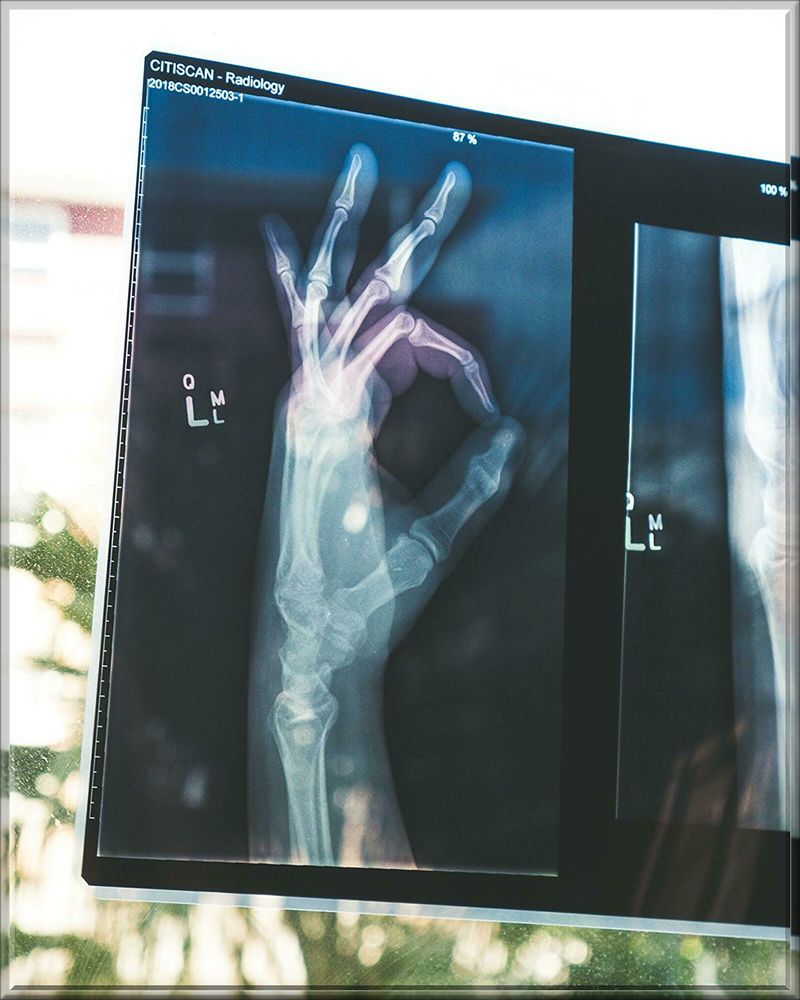

俺は

この病院で最初にまた

レントゲンを取られ

精密検査を行った。

その結果

右上の奥歯が

上顎の頬の内側の空洞に

引っ込んでる事が解った。

しかも4本も引っ込んでて

全部抜かないとダメだと

先生に言われてしまった。